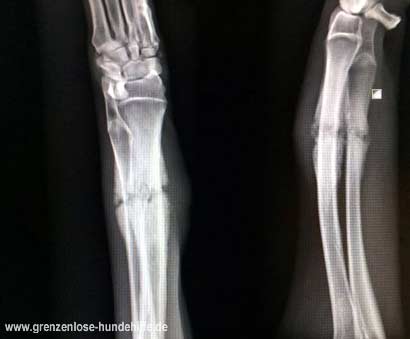

Zamira, eine ca. 9 Monate alte Kangal Hündin, wurde stark humpelnd gefunden und im Tierheim abgegeben.

Da sie ihr Bein quasi gar nicht benutzte, lag die Vermutung nahe, dass das Bein gebrochen war!

Um Gewissheit zu erlangen haben wir sie umgehend einem Tierarzt vorgestellt, der unseren Verdacht leider bestätigte!

Die junge Hündin wurde wahrscheinlich einfach ausgesetzt und musste mit einer ca. 4 Wochen alten, kaum verheilten Fraktur leben!!!

Es ist unbeschreiblich, welch immense Schmerzen die Süße ertragen hatte und mit welcher Gleichgültigkeit und Verantwortungslosigkeit sie "entsorgt" wurde.

Durch einen externen Fixateur wurde ihr Bein stabilisiert und kann nun endlich richtig verheilen, damit Zamira in eine unbeschwerte Zukunft auf 4 gesunden Pfoten gehen kann!